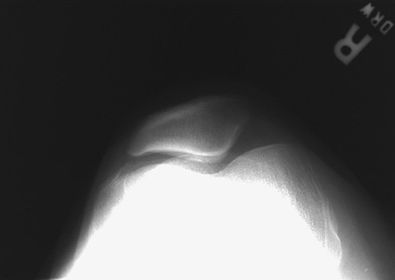

A. patella B. femoropatellar joint C. lateral condyle D. patellar surface E. medial condyle